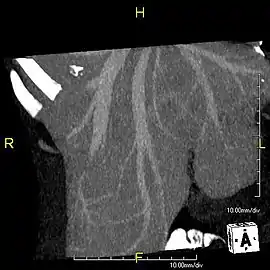

Axial CT image showing anomalous hepatic veins coursing on the liver's subcapsular anterior surface[70]

Maximum intensity projection (MIP) CT image as viewed anteriorly showing the anomalous hepatic veins coursing on the anterior surface of the liver

Lateral MIP view in the same patient as previous image